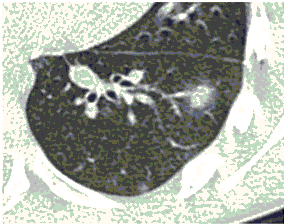

2. Наличие клинических проявлений, указанных в п. 1, в сочетании с характерными изменениями в легких по данным компьютерной томографии (КТ) (см. Приложение 1 настоящих рекомендаций) вне зависимости от результатов однократного лабораторного исследования на наличие РНК SARS-CoV-2 и эпидемиологического анамнеза.

- Изменения при КТ (рентгенографии), типичные для вирусного поражения (объем поражения минимальный или средний; КТ 1-2)

- Изменения в легких при КТ (рентгенографии), типичные для вирусного поражения (объем поражения значительный или субтотальный; КТ 3-4)

- Изменения в легких при КТ (рентгенографии), типичные для вирусного поражения критической степени (объем поражения значительный или субтотальный; КТ 4) или картина ОРДС.

КТ имеет высокую чувствительность в выявлении изменений в легких, характерных для COVID-19. Применение КТ целесообразно для первичной оценки состояния ОГК у пациентов с тяжелыми прогрессирующими формами заболевания, а также для дифференциальной диагностики выявленных изменений и оценки динамики процесса. КТ позволяет выявить характерные изменения в легких у пациентов с COVID-19 еще до появления положительных лабораторных тестов на инфекцию с помощью МАНК. В то же время, КТ выявляет изменения легких у значительного числа пациентов с бессимптомной и легкой формами заболевания, которым не требуется госпитализация. Результаты КТ в этих случаях не влияют на тактику лечения и прогноз заболевания при наличии лабораторного подтверждения COVID-19. Поэтому массовое применение КТ для скрининга асимптомных и легких форм болезни не рекомендуется.